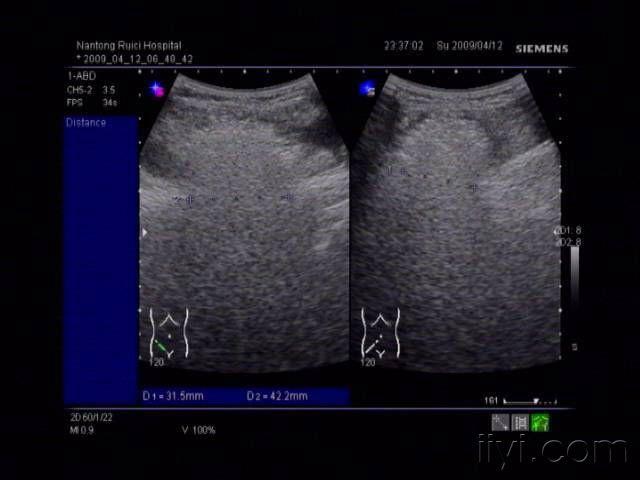

腹壁疝超声描述,腹壁疝超声图片

腹壁疝体表超声图

腹壁疝超声图片

腹壁疝彩超报告图片